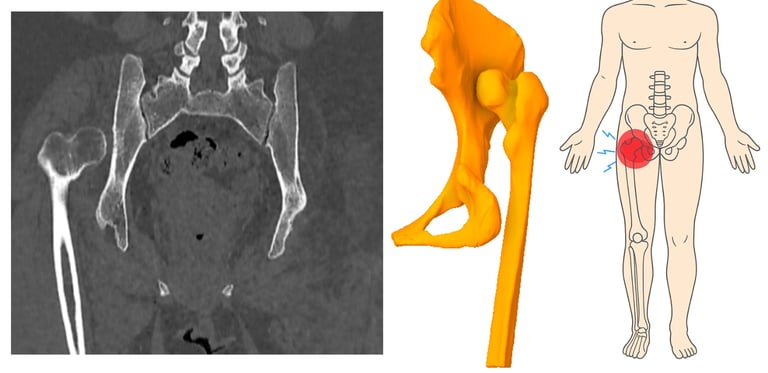

La cadera es vital para actividades cotidianas como trabajar, caminar y hacer ejercicio. Este estudio demostró la importancia de recopilar información sobre los tipos de cadera flotante para analizar la afección y establecer una metodología para el desarrollo de prótesis. Esta investigación facilita la creación de prototipos de prótesis de cadera debido a la complejidad y singularidad de las intervenciones necesarias, que pueden variar según la zona de las lesiones, que se producen ipsilateralmente y en dos huesos diferentes.

Radiografía de fractura de cadera y su localización.